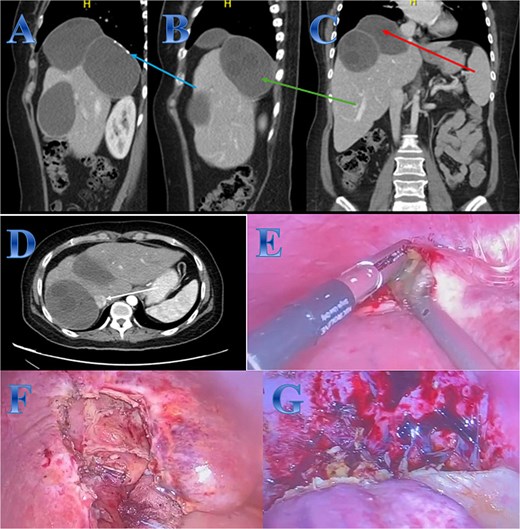

A 54-year-old woman presented with upper abdominal pain with a history of PAIR procedure before 5 years. The abdominal CT scan with contrast highlights left hepatic lobe calcified exophytic CE (Fig. 3).

Case 3. (A) Coronal CT cut of the abdomen at venous phase showing a well-defined cystic lesion (hydatid cyst) seen at the left hepatic lobe, showing calcifications, the lesion seen partially exophytic from the liver and abutting the lesser curvature of the stomach. (B & C) The hydatid cysts that were resected from the liver (C) and from the greater Omentum (B). (D) After resection the liver hydatid cyst was opened to examine the content of the cyst which is showing jelly like structure.

For a left lateral hepatic resection, a subcostal incision allowed exploration of the calcified cystic mass, which affected segments 2 and 3 of the liver and was significantly adhered to the diaphragm and stomach. A left lateral segment (segments 2 and 3) mobilization procedure required dividing the falciform, left triangular, and left coronary ligaments. A harmonic scalpel, in combination with bipolar coagulation, completed the resection of the recurrent hydatid cyst without damaging its internal contents (Fig. 3).